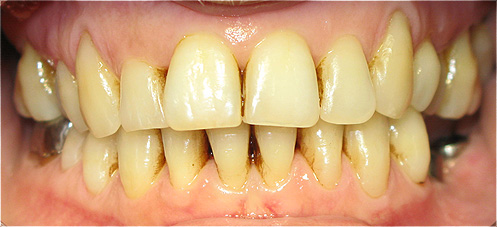

Resultado de colocação de implante dentário na Clínica São Filinto

A colocação de implantes dentários de titânio é, atualmente, a melhor forma de substituir os dentes ausentes, pois não só lhe devolve a estética dentária perdida, como também a sua função mastigatória.

A utilização de novos materiais nas coroas implanto-suportadas, como o zircónio, e as novas técnicas laboratoriais avançadas, em conjunto com a utilização de softwares especializados na construção das coroas dentárias, aumenta ainda mais a estética dentária porque confere ao dente um aspeto muito natural.